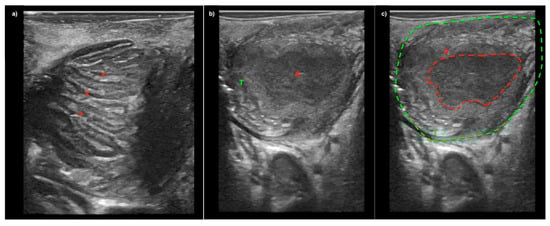

A Novel Technique for Intraoral Ultrasound-Guided Aspiration of Peritonsillar Abscess

2. Materials and Methods

3. Results